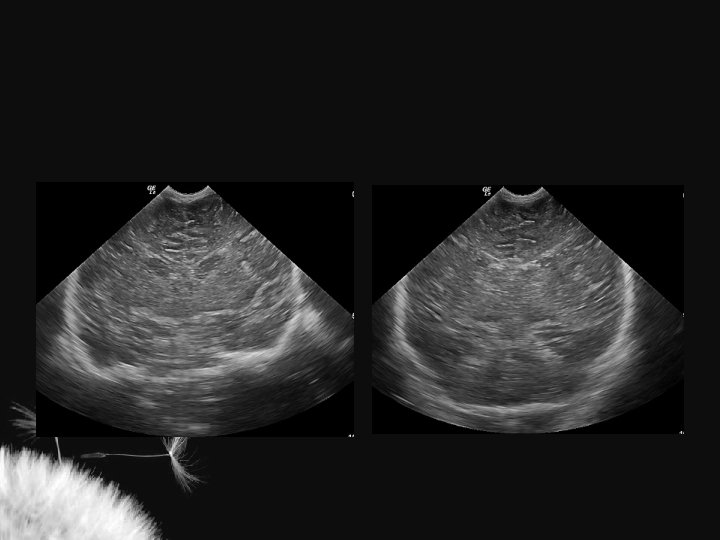

LESÃO HIPÓXICO-ISQUÊMICA NO RN TERMO